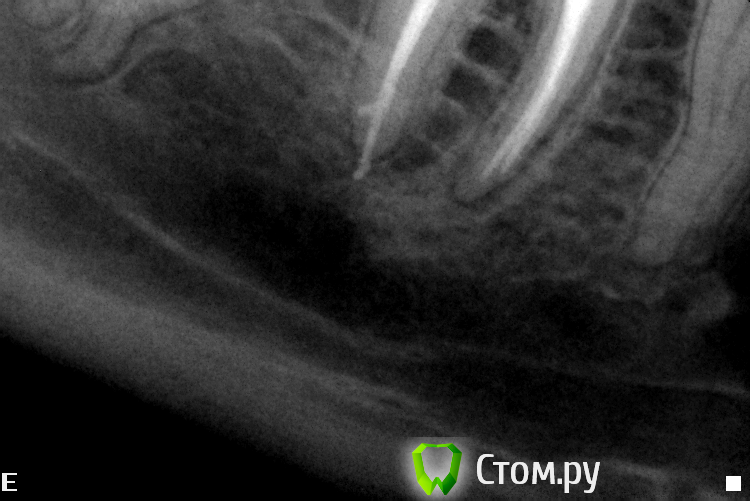

Slaggy Опубликовано 2 октября, 2014 Автор Поделиться Опубликовано 2 октября, 2014 Почётно ! Как извлекали ? Сколько по времени ? Почему без коффердама ? Руками, соник, ультрасоник, бино 3.5Гемор, если чесно, но я, вопреки мнению пациента полез в зуб на поиски МВ2, пришлось сделать все, чтоб исправить.4 посещения:1 - посмотрел на лунку, сказал что не она, полез в зуб, нашел мв2, снимок (не все удается скопировать, а база очень ограничена - неудачная программка стоит), непонравился МВ, прошел и снимок2 - прошел МВ2, сломал в МВ желтый Н, наломал кучу в МВ3 - достал все кроме первого (в клинике нет внутриканальных инструментов, решил принести свой эндочак и u-files)4 - принес свой чак, достал последний и запломбировал МВ и пломба. В клинике общий эндоинструмент, поэтому ломаки бывают непредсказуемые.В свой первый день тут я выкинул все. Весь ручной и машинный инструментарий - весь повитый был.Сейчас начальство стало прислушиваться (я ж их блатных лечу), скоро налажу все. 2 Ссылка на комментарий

Slaggy Опубликовано 2 октября, 2014 Автор Поделиться Опубликовано 2 октября, 2014 (изменено) Ну почётно,что тут скажешь. Вы сами знаете, что подтянуть. Но зуб я всё -таки покрыл бы в итоге,когда дойдёт до протезирования. Да все тянуть надо, при этом 10-12 пациентов в день.Сегодня 3 эндотрупа моляров работаны, Один свежий пульпит , 3 сдачи/фиксации, 1 съемник и 1 профгигиена. Про эндотрупы: ушел под кальцийКстати, это еще приличные снимки. обычно любуюсь апикальной третью корней ))))Тут в резорцинке косяк произошел. Видимо при конденсации проскочила гутта ((( расстроился.Но её хирург протежировал, Поговорю с ним, если апико сделает, то я не полезу. Изменено 2 октября, 2014 пользователем Slaggy 1 Ссылка на комментарий